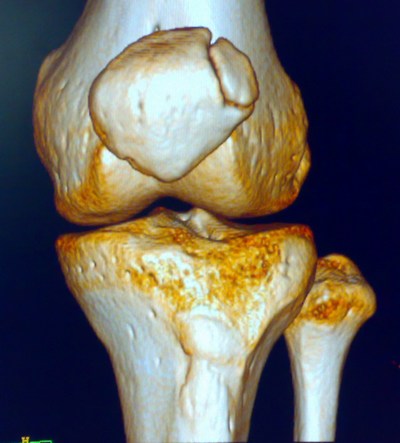

标题: X7705:上传CT结果:二分髌骨 [打印本页]

标题: X7705:上传CT结果:二分髌骨

上传ct结果:二分髌骨

符合二分髌骨表现。